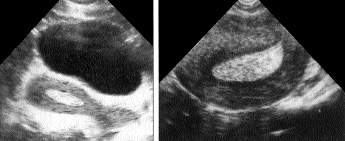

Медицинская диагностика: Гиперплазия эндометрия на УЗИ